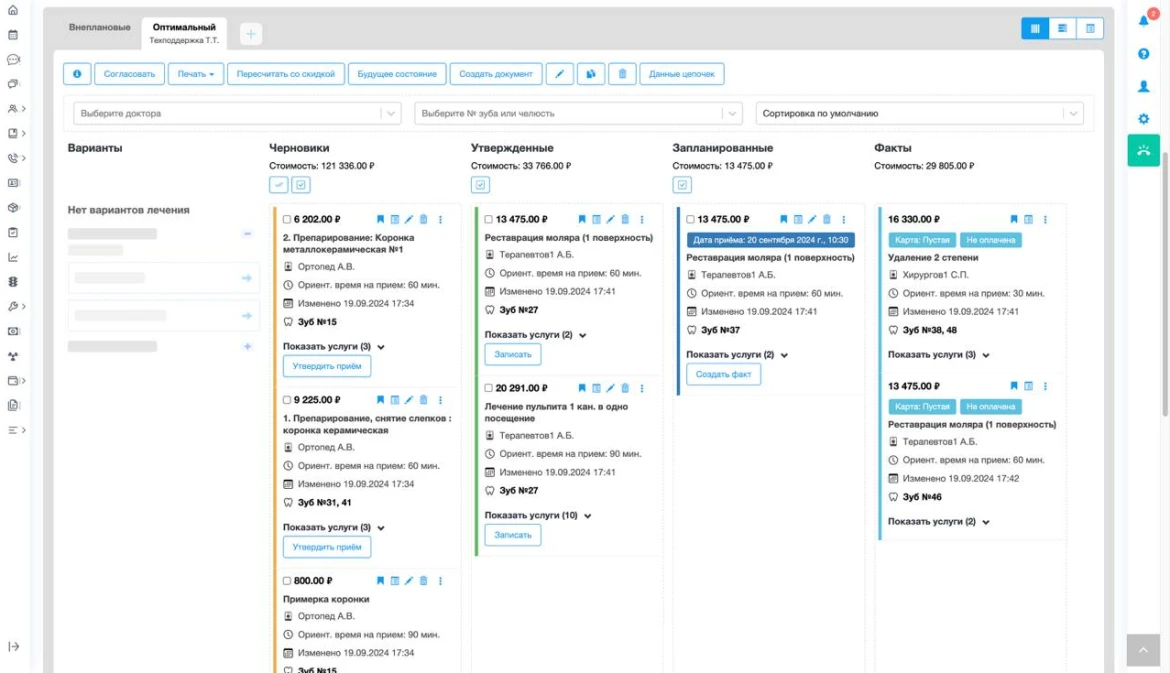

- Электронные карты пациентов: Хранение полной информации о пациентах, включая историю заболеваний, результаты анализов и планы лечения.

- Финансовый учет: Ведение учета платежей, расчетов со страховыми компаниями и создание финансовых отчетов.

- Аналитика и отчеты: Инструменты для анализа посещаемости, эффективности лечения и финансовых показателей, что позволяет принимать обоснованные решения.

| Управление заказами | да |